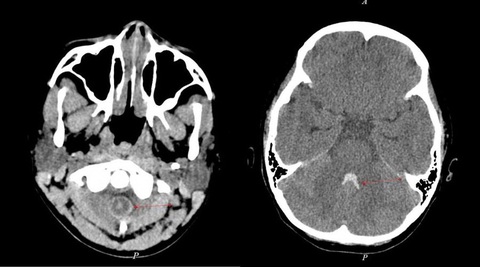

Trước đó, N. chỉ có các biểu hiện đau đầu nhẹ, sau khoảng một tuần thì xuất hiện nôn mửa. Kết quả chụp CT của N. cho thấy xuất huyết trong não thất và khoang dịch não tủy ở cột sống cổ.

Kết quả CT xuất huyết trong não thất và khoang dịch não tủy ở cột sống cổ của bệnh nhân Đ.N. (10 tuổi) - Ảnh: P.T.